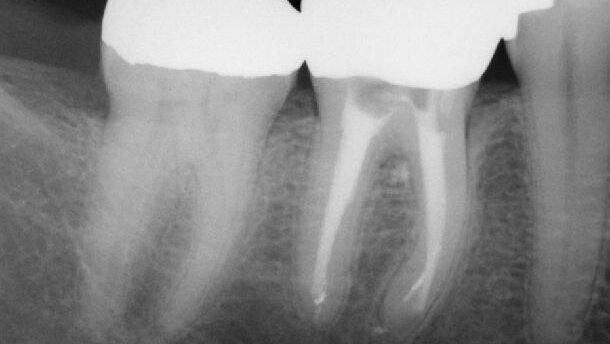

Sự hiện diện của viêm quanh cuống trước điều trị là một yếu tố làm giảm tỉ lệ thành công. Không viêm quanh cuống, tỉ lệ thành công trong 10 năm là 92-98% cho cả điều trị tủy ban đầu và điều trị tủy lại. Trước phẫu thuật, với sự hiện diện của viêm quanh cuống, có sự giảm tỉ lệ thành công từ 74-86% qua 10 năm.[5] Từ đó, rõ ràng có thể đạt được lành thương nội nha thông qua thủ thuật điều trị tủy lại, cho phép chúng ta duy trì răng tự nhiên của bệnh nhân. (Hình 1a-c) Mặc dù lựa chọn điều trị thay thế trên lâm sàng là cấy ghép implant có thể cung cấp 1 phương pháp hiệu quả để thay thế răng mất, duy trì sự lành mạnh của răng tự nhiên vẫn còn là mục tiêu tổng quát.

Hình 2[8] cho thấy giải phẫu ống tủy phức tạp trước phẫu thuật (vùng màu xanh) và số lượng tối thiểu của thành ống tủy được làm sạch hoàn toàn khi thao tác dụng cụ (vùng màu đỏ). Vùng xanh còn lại minh họa khoảng trống có thể chưa được điều trị, do đó tạo ra 1 nguồn vi khuẩn và chất nền hỗ trợ (supporting substrate) cho nhiễm khuẩn trong ống tủy. Chất nền tiềm tàng (potential substrates) được tìm thấy bên trong ống tủy và giúp vi khuẩn sống sót có thể gồm mô tủy chưa được điều trị, màng biofilm và dịch mô. Nó có thể xuất hiện trong ống tủy do sự trám bít kém và sự sinh sôi vi khuẩn. Sự hiện diện của trám bít kém, vi khuẩn và chất nền tốt cho sự phát triển của chúng tạo điều kiện lí tưởng cho các bệnh lý và viêm nhiễm dai dẳng.[9]

Vi khuẩn hiện diện trong nhiễm trùng ban đầu của ống tủy khác biệt rõ rệt với vi khuẩn lây nhiễm vào răng được điều trị trước đó. Trước điều trị là hệ đa vi khuẩn với số lượng bằng nhau của vi khuẩn Gram âm và Gram dương. Sau điều trị vi khuẩn Gram âm chiếm ưu thế [10] và chúng có thể sống sót trong môi trường khắc nghiệt và kháng với nhiều phương pháp điều trị.